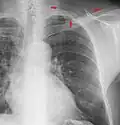

• The silhouette sign is especially helpful in localizing lung lesions. (e.g., loss of right heart border in right middle lobe pneumonia),[9]